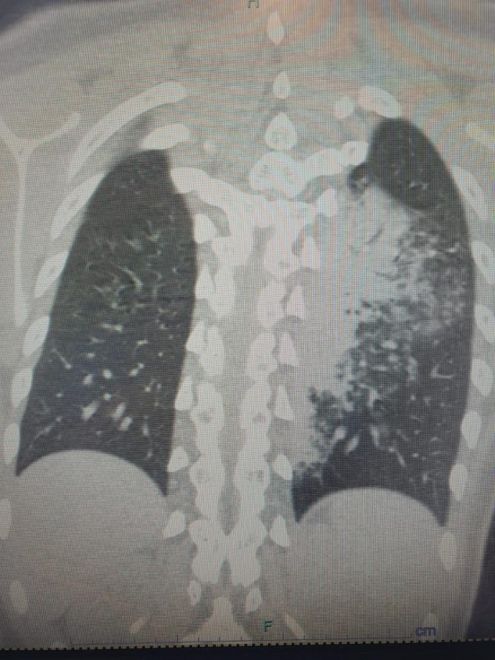

Göğüs Hastalıkları Uzmanı Prof. Dr. Şevket Özkaya, özellikle otel ve tatil köylerinde konaklayan kişiler arasında “beni klima çarptı” diyen neredeyse her iki kişiden birinde bu hastalıkların saptandığını belirtti. Prof. Dr. Özkaya, bu durumdan en çok etkilenenlerin ise çocuk yaş grubu olduğunu vurgulayarak, “Ciddi sayıda, daha önce görülmemiş derecede çocuk bronşiti ve zatürresi vakaları görmeye başladık. Hatta COVID-19 salgınında, çocuk yaş grubunda COVID-19 virüsüne bağlı bu kadar çok zatürre görmüyorduk. Son günlerde; ‘Legionella’ bakterisinin, çocuk yaş grubunda COVID-19’a oranla çok daha fazla zatürreye neden olduğunu görüyoruz” diye konuştu.

Legionella pneumophila isimli bakterinin klimalardan üremesi sonucunda hastalığın ortaya çıktığını belirten Prof. Dr. Özkaya, bu hastalığın kronik rahatsızlığı olanlarda ölümcül olabileceğini ve yaşlı, kronik hastalığı olan vatandaşların dikkatli olmaları gerektiğini hatırlattı.

Özellikle klimaların iyi temizlenmesi gerektiğini belirten Prof. Dr. Özkaya, klima zatürresinde şikayetlerin daha az olduğu için grip gibi eklem ağrıları, ateş, halsizlik, ishal gibi hafif soğuk algınlığı belirtileriyle seyrettiği için çok fazla anlaşılmayabileceğini söyledi. Kronik hastalığı olanlarda hayati sonuçlar da doğurabileceğini belirten Özkaya, “Pandeminin bitmesiyle beraber ani ısı değişikliklerine, soğuktan sıcağa geçişlere ve klimalara maruz kalmak, grip ile karıştırılabilir ve önemsenmeyebilir. Çocuklar ise ne hissettiklerini anlatamadıkları için uzamış öksürük ve ateş şikayeti ile doktora başvurduklarında ciddi zatürre vakaları ile karşı karşıya kalırlar” dedi.